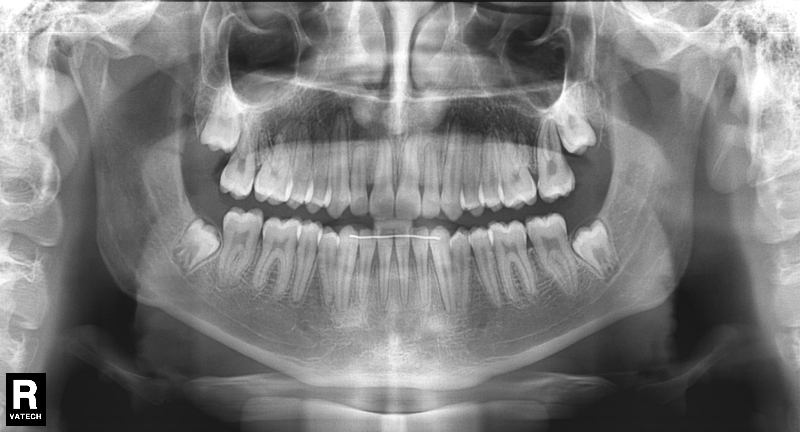

El paciente E.A. acude a nuestra consulta por diastema inferior y ausencia de contactos en los sectores laterales.

Chica de 17 años tratada en 1 año con stripping en los dientes inferiores